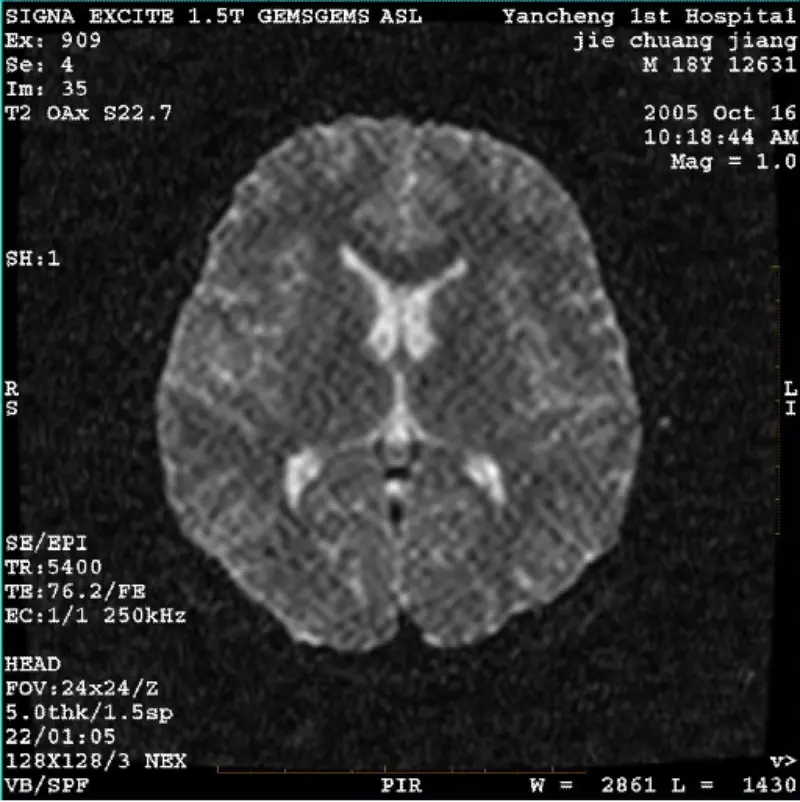

Leigh Nios moCÓRAS: 1.5T Signa Twin Excite II (Leagan Bogearraí 11.0M4) FADHB/SIMPTO DWI (mód súmáil agus modh iomlán) agus fiesta (modh súmála agus modh iomlán) íomhá a bhfuil déantán infheicthe reticulate nó corduroy is cuma nuair a úsáidtear corn corn nó ceann coil, is cosúil gnáth-íomhá eile gnáth